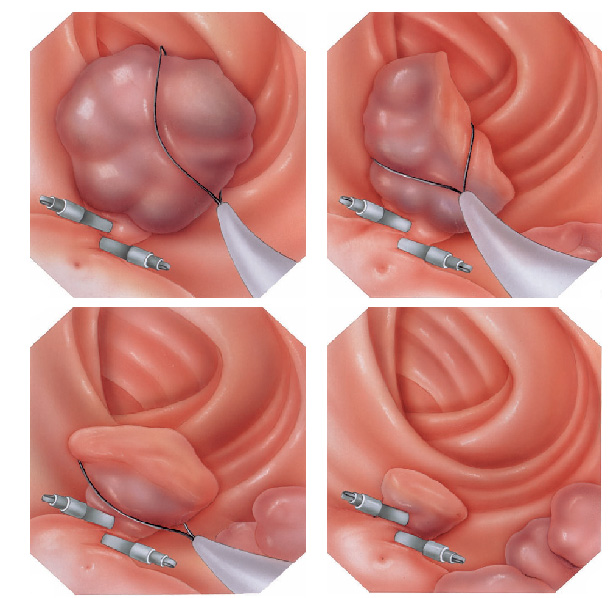

Mucosectomia é o procedimento realizado quando há necessidade de retirada de lesões maiores do trato gastrointestinal.

O exame de Mucosectomia é realizado através de injeção de liquido embaixo da lesão, através de uma agulha específica. Com isso a lesão se destaca das camadas mais profundas do intestino, diminuindo o risco de perfuração.

A retirada da lesão é feita com uma alça de polipectomia e o material é encaminhado para estudo anatomopatológico (no microscópio) da mesma forma que ocorre nas biópsias.

O que é a polipectomia?

A polipectomia é a remoção completa de um pólipo permitindo assim o diagnóstico exato e muitas vezes a cura do próprio problema. Existem várias técnicas para a realização do procedimento que dependem do tamanho e do tipo de pólipo a ser ressecado.

Alguns pólipos não possuem a base alongada (pedículo), estes são chamados de pólipos sésseis. A remoção destes pólipos possui risco maior de perfuração do órgão pois como são planos ficam muito próximos da parede externa do órgão.

Mucosectomia

Para diminuir este risco, injeta-se com um uma agulha uma solução abaixo do pólipo para que ele levante e fique mais longe da parede do órgão. Após isto passa-se a alça diatérmica e realiza-se o

procedimento de polipectomia.

A ablação por radiofrequência usa calor para remover tecido pré-cancerígeno do esôfago de Barrett. A tecnologia do sistema de ablação por radiofrequência é projetada para a remoção de tecido afetado por Barrett, preservando o tecido saudável subjacente.Tratamento do Esôfago de Barrett com Mucosectomia

A mucosectomia é uma técnica empregada para ressecção do Esôfago de Barrett com lesões displásicas visíveis (pré-cancerígenas ou cancerígenas iniciais). Geralmente essa ressecção é realizada através da colocação de ligaduras elásticas, seguido da apreensão e corte com alça de polipectomia. O produto da ressecção é enviado para a análise histológica pelo patologista, a fim de verificar se o paciente está curado e para definir como será o acompanhamento no futuro.O que é gastrostomia endoscópica?